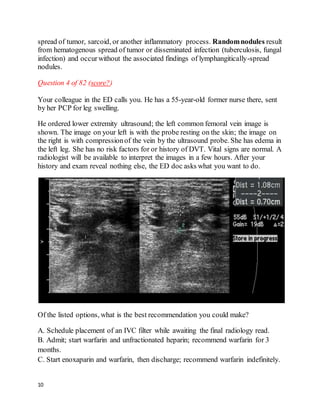

Question 4 of 82 (score?)

Your colleague in the ED calls you. He has a 55-year-old former nurse there, sent

by her PCP for leg swelling.

He ordered lower extremity ultrasound; the left common femoral vein image is

shown. The image on your left is with the probe resting on the skin; the image on

the right is with compressionof the vein by the ultrasound probe. She has edema in

the left leg. She has no risk factors for or history of DVT. Vital signs are normal. A

radiologist will be available to interpret the images in a few hours. After your

history and exam reveal nothing else, the ED doc asks what you want to do.

Of the listed options, what is the best recommendation you could make?

A. Schedule placement of an IVC filter while awaiting the final radiology read.

B. Admit; start warfarin and unfractionated heparin; recommend warfarin for 3

months.

C. Start enoxaparin and warfarin, then discharge; recommend warfarin indefinitely.

11

D. Get dedicated Doppler ultrasound of the leg veins.

E. Pulmonary angiogram.

We feelthat C is the best answer.

This is a proximal, unprovoked, asymptomatic DVT. The vein should compress

completely; this one does not, and has an echogenic area in the lumen (it should be

homogenously jet-black inside).

Generally speaking, recurrence rate after unprovoked DVT is similar between

people with and without identifiable hypercoagulable states. ACCP

recommendations for people with unprovoked proximal DVT without PE are that

anticoagulation be continued "long-term" (i.e., indefinitely), if the patient is

amenable after a risk/benefit discussion(Grade 1A, "Antithrombotic Therapy for

VTE Disease," Section 2.1.2). ACCP also recommends warfarin be begun the same

day as enoxaparin.

There is growing acceptance of treating asymptomatic DVT on an outpatient basis

"if possible" (Grade 1C ACCP recommendation), which we take to mean the

patient is stable, can self-inject enoxaparin, and close follow-up can be arranged

for INR checks.